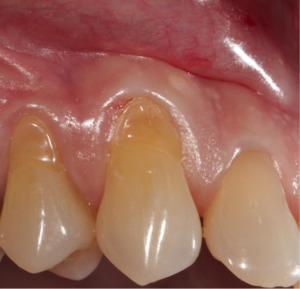

Abrasion occurring on the cervical margins from the effects of friction from toothbrushing and abrasive toothpastes